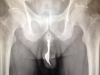

Médicos australianos consiguieron sacar del interior del pene de un hombre un tenedor metálico de 10 centímetros de largo.... (seguir leyendo)